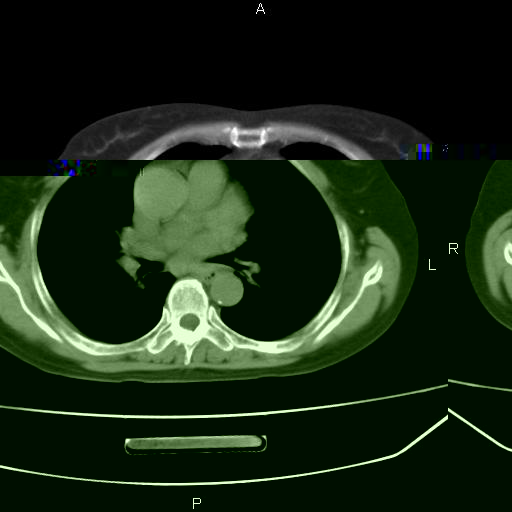

患者,女,66岁。健康体检胸部透视发现右上肺片状阴影。既往无不适,患者自诉三个月前曾有低热病史体温37.5左右一周。用药后缓解。至今无其它不适。请老师们指导指导。

考虑:右肺上叶周围型肺癌(分叶状肿块+砂粒状钙化+胸膜尾征)。

病灶见明显分叶、大小较大(大于3cm?),老年人,多考虑:肺癌,建议穿刺活检。

典型的中心型肺癌,尖段支气管阻塞。

右肺上叶周围型肺癌可能性大。

考虑:右肺上叶周围型肺癌